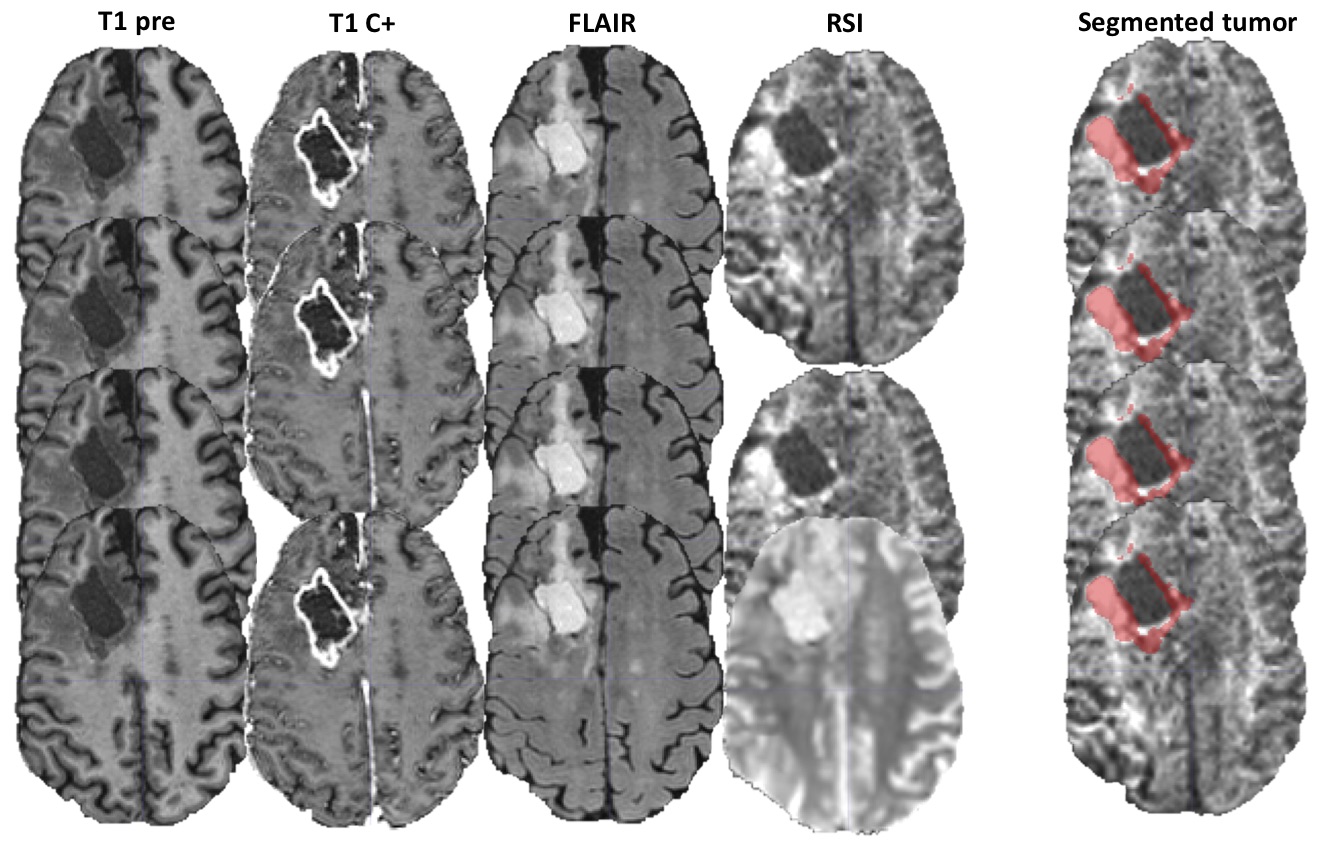

An example of segmentation for a cellular non-enhancing tumor case is shown in Fig 1. While the regions of FLAIR hyperintensity in the splenium of the corpus callosum and bilateral parieto-occipital white matter did not demonstrate significant enhancement, they showed increased RSI cellularity signal compatible with cellular infiltrative tumor (Fig 1A). These regions were segmented as tumor tissue in Fig 1B. An example of segmentation for a case with only post-treatment changes is shown in Fig. 2. The red arrow in Fig 2A demonstrated peripheral nodular enhancement at the anterior margin of the surgical cavity but the RSI cellularity map (blue arrow) did not demonstrate RSI cellularity signal in the enhancing regions or surrounding edematous tissue, suggesting post-treatment changes rather than recurrent tumor. This was confirmed on the follow-up scan (Fig 2B) where this region of nodular enhancement improved (green arrow) and tissue necrosis increased (yellow arrow) as shown by the very high RSI signal. Tumor segmentations with several variations of the Deep Learning model with different inputs are shown in Fig 3 for an individual test subject and the average Dice scores over the entire testing set is shown in Table 1. Adding RSI cellularity to the combination of T1 pre, T1C+ and FLAIR sequences increased the Dice score from 0.50 to 0.65. Although adding ADC to T1, T1C+, and FLAIR sequences also increased the Dice score, the increase was less pronounced than with RSI (0.60 ± 0.31 vs. 0.65 ± 0.24)." Fig 4 demonstrates an inverse relationship between volume of enhancing cellular tumor (both T1C+ and RSI positive) and the overall survival for patients with RSI scans within 180 days following surgical resection (n=20).

Fig. 3. Tumor segmentations for several iterations of the Deep Learning model. The MRI volumes used are shown in the first four columns while the resulting tumor segmentation is shown in the fifth column (right). The first row represents the full model while other rows represent different iteration for comparison: no RSI, no T1 C+, and high b-value DWI rather than RSI respectively for row 2 to 4.